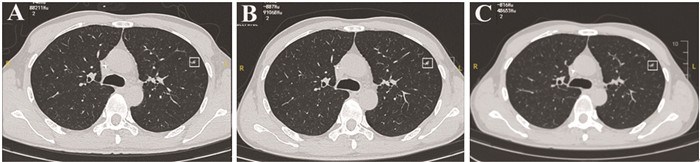

Tetta等[11]在软组织肉瘤肺部结节的恶变率判断中发现临床特征联合CT影像学特点能够展现出更好的预测转归能力。本中心通过对比恶性IPN与良性IPN的胸部CT影像学特征发现,恶性IPN直径平均大小为6.969±1.118 mm,高于良性组,见图 3。这一点与Pontes等[12]研究一致。这也意味着判断良恶性结节最主要的影像学特征首先是其直径,肺部结节的直径越大,结节为恶性的可能性也越大[13]。本研究中,我们发现恶性IPN多为散发、类圆形,多以实性及混合性为主。因此对于伴有IPN的高级别STS患者具有较大的IPN直径、类圆形、实性或混合性可能具有更高的恶变倾向。同时,我们还注意到,治疗后新发的IPN恶性结节的可能性更高。除此之外,IPN发现间期是影响恶性转归的IPN高级别STS患者的独立因素,相较于初筛时发现IPN,治疗后新发的恶性IPN会导致更差的生存,可能与肿瘤细胞对化疗方案耐药有关。因此对于高级别STS患者肺部IPN,我们中心采取根据结节级别分级随访的策略。伴有上述高危因素的合并IPN高级别STS患者推荐每月复查一次胸部CT,直径大于10 mm或出现数量增加后诊断为转移灶,进行早期干预治疗。对于不伴有上述高危风险的合并IPN高级别STS患者推荐每2~3月复查一次,6月后病灶无明显改变,可转为常规随访,见图 4。

图 3 一例高风险IPN高级别STS患者的胸部CT随访Figure 3 Chest CT follow-up of a patient with high-grade STS and high-risk IPNThis patient was a 46-year-old male diagnosed with high-grade angiosarcoma in left leg. Eight months after the diagnosis of high-grade angiosarcoma, the patient underwent chest CT examination and showed a solid quasi circular nodule that had a clear boundary and a diameter of approximately 7 mm in the middle lobe of the right lung (A). It was included in the high-risk STS IPN follow-up. One month later, chest CT follow-up showed that the diameter of the nodule in the middle lobe of the right lung increased to 10 mm, presenting as a mixed-density nodule with a clear boundary (B). One month later, a follow-up CT scan of the chest revealed that the diameter of the nodule in the middle lobe of the right lung increased to 14 mm, presenting as a full-solid-density nodule with clear boundaries (C). The high-risk IPN was determined as metastatic, and the patient was treated with anlotinib. The patient is currently surviving well.![]() 图 4 一例低风险IPN高级别STS患者的胸部CT随访Figure 4 Chest CT follow-up of a patient with high-grade STS and low-risk IPNThis patient was a 67-year-old male diagnosed with undifferentiated sarcoma of the left hip joint. Sixteen months after the diagnosis of undifferentiated sarcoma, the patient underwent chest CT examination that showed an irregular, ground glass nodule with a diameter of approximately 5 mm in the anterior segment of the left upper lobe and was included in the low-risk soft tissue sarcoma IPN follow-up (A). Two months later, chest CT follow-up showed that the size and nature of the ground glass nodule in the anterior segment of the left upper lobe were the same as before (B). After three months, chest CT follow-up showed no changes in the size and nature of the ground glass nodule in the anterior segment of the left upper lobe(C). The possibility of metastasis was ruled out, and regular follow-up was conducted every six months.

图 4 一例低风险IPN高级别STS患者的胸部CT随访Figure 4 Chest CT follow-up of a patient with high-grade STS and low-risk IPNThis patient was a 67-year-old male diagnosed with undifferentiated sarcoma of the left hip joint. Sixteen months after the diagnosis of undifferentiated sarcoma, the patient underwent chest CT examination that showed an irregular, ground glass nodule with a diameter of approximately 5 mm in the anterior segment of the left upper lobe and was included in the low-risk soft tissue sarcoma IPN follow-up (A). Two months later, chest CT follow-up showed that the size and nature of the ground glass nodule in the anterior segment of the left upper lobe were the same as before (B). After three months, chest CT follow-up showed no changes in the size and nature of the ground glass nodule in the anterior segment of the left upper lobe(C). The possibility of metastasis was ruled out, and regular follow-up was conducted every six months.Cipriano等[14]回顾性分析青少年肉瘤患者肺部结节对生存的影响发现,除肿瘤大小外,结节的数量也与预后相关。Yamamoto等[15]回顾性分析接受肺转移切除术的135例肉瘤患者生存预后发现无病生存间期、最大肺部转移灶直径以及肺部病灶数量与预后相关。Rissing在研究中发现IPN直径大于5 mm预后更差[8],而Mayo的研究发现生存预后似乎与结节大小无关[10]。欧洲软组织肉瘤研究组对316例儿童非转移性横纹肌肉瘤患者进行研究,发现IPN不影响横纹肌肉瘤患者的预后,没有必要对诊断时存在IPN的横纹肌肉瘤患者进行活组织检查或预先诊断[16]。本中心发现年龄与结节发现间期是影响伴恶性转归的IPN高级别STS患者IPN确诊后生存期的独立因素。年龄较大以及治疗后发现IPN导致患者具有更差的生存预后。这也提示高级别STS病理类型异质性大,影响其肺部结节患者的生存预后也不尽相同。本研究受限于较少的样本量,同时诸多研究间缺乏统一的纳入及研究因素,因此日后的研究中对于不同病理的STS伴IPN患者作出亚组分析将更有效的研究生存影响因素。